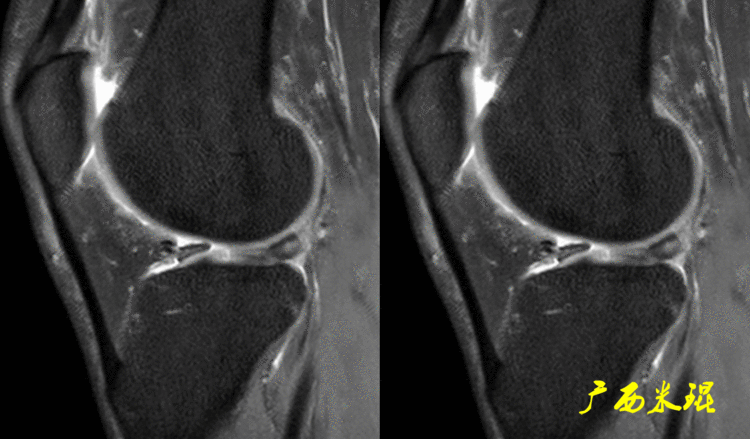

下面这张MR冠状位显示为内侧半月板后角的假桶柄,其母体(图片中内侧的那一部分半月板)并没有变小、形态及信号均正常。

下面这张MR冠状位显示为外侧半月板后角的假桶柄,尽管在髁间窝发现半月板信号,但其母体(图片中外侧的那一部分半月板)并没有变小、形态及信号均正常。